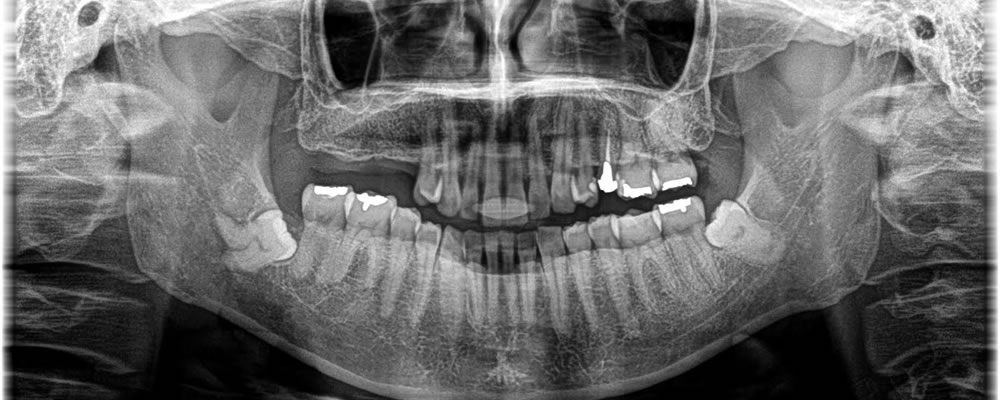

欠損部分に実施したインプラント治療の症例

こちらの患者さまは以前に奥歯を抜歯し、歯のないところにインプラント治療を行いたいという事で来院されました。

下顎の奥歯が挺出してきていましたが、そこは触らずに行いたいとの希望でした。上顎の骨の厚みが確保されていたため、少し深めにインプラント体の埋入を行い、骨の形を整えるという方法で手術を進めました。